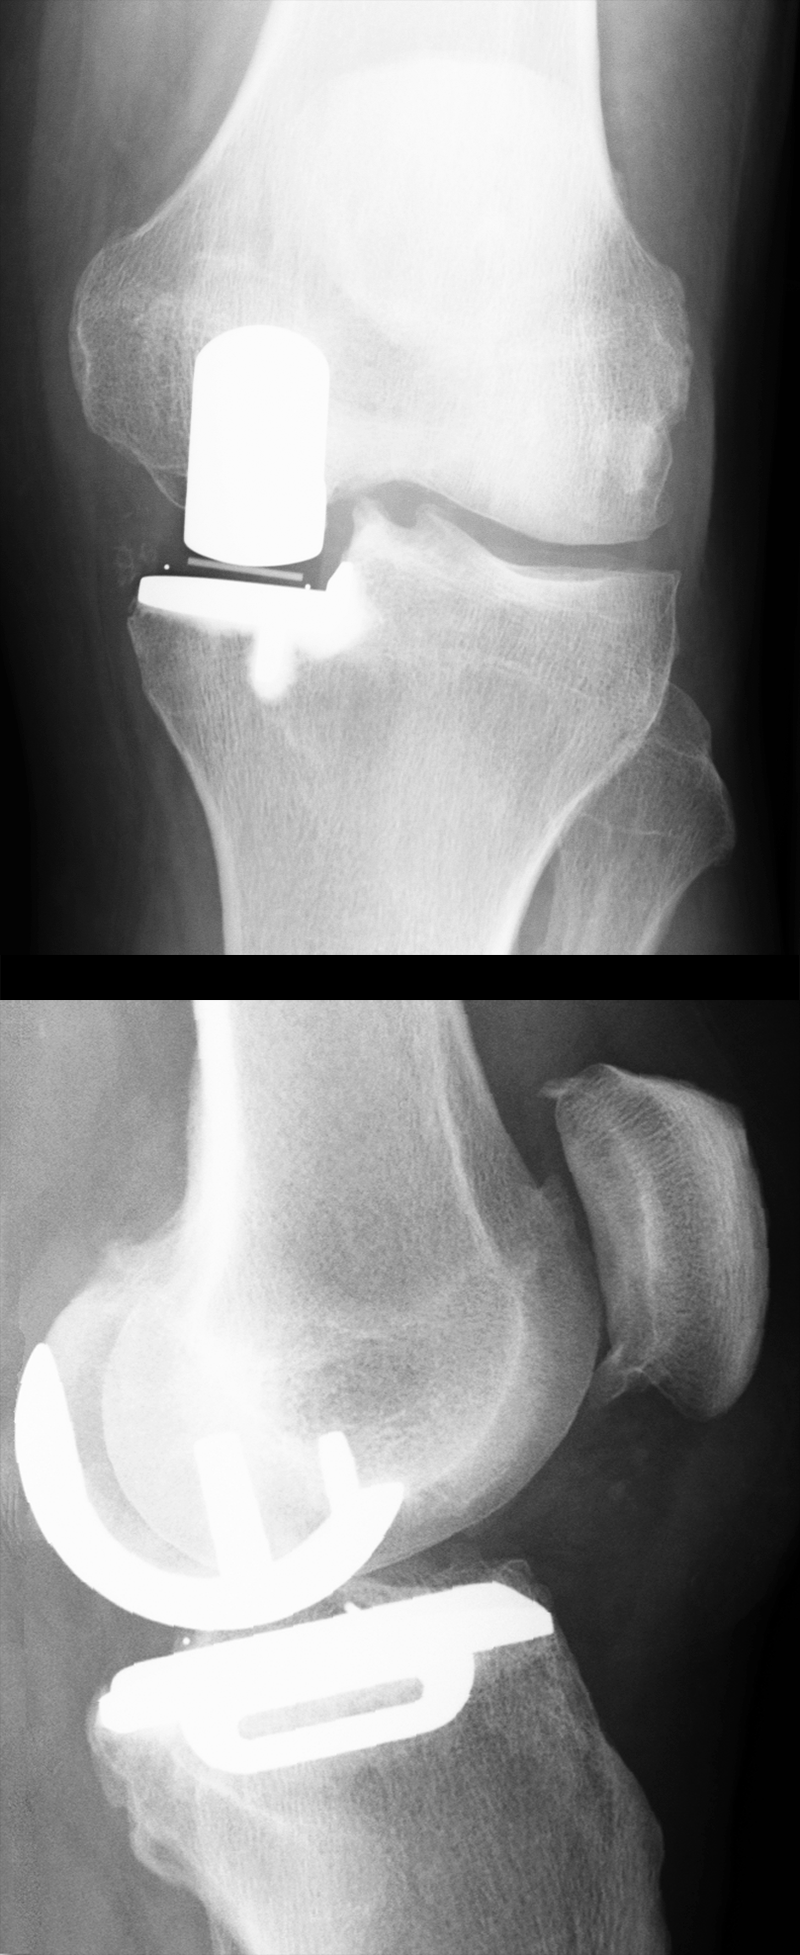

Schlitten-Endoprothese – groß